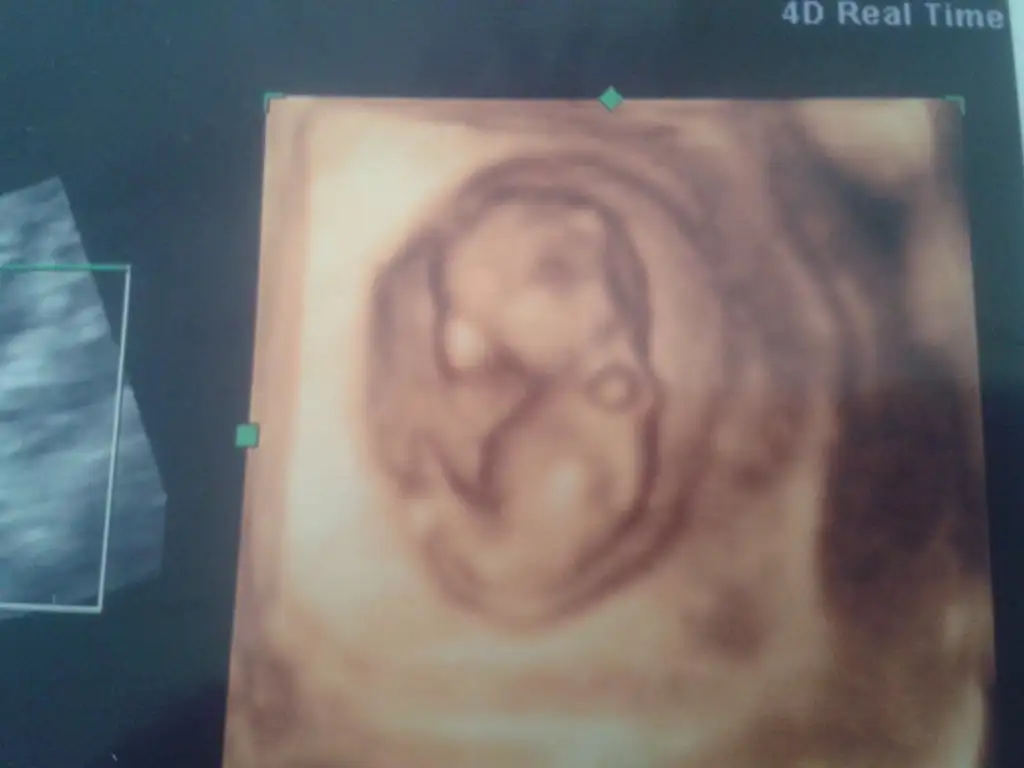

bu resim 8. haftanın sonu 9.haftanın ilk günüsoldaysa erkek, sağdaysa kız buradaki teoriye göre ama 7-8-9 haftalık ultrason görüntüsü olması gerekiyormuş. benim 7.hafta soldaydı 10.hafta sağa geçti. seninki kaç haftalık

bence sağda görünüyor ama parlak yer dediğini anlamadım başka fotoğrafı yok mu çok bulanık çıkmış doktorun boyunu ölçtüğü 2 nokta arası olanlarda daha rahat anlaşılıyor.Kizlar bu ultrasona gore ne sizce tahminlerinizi bekloyorum 8 haftalik burda altta gorunen parlak yer melegim

Canım baktım bebeğin sağda ama burada kesenin konumuna göre tahmininde daha erken (7-8-9. haftalar için)görüntüsü olması lazım. Benim bebeğim 7. haftada soldaydı 10.haftada sağa geçti. o yüzden yanıltabilir.cnm benim bebegim içinde yorum yaparmısın 13+1

çok teşekkürler cnm bu 8+5 günlüktüCanım baktım bebeğin sağda ama burada kesenin konumuna göre tahmininde daha erken (7-8-9. haftalar için)görüntüsü olması lazım. Benim bebeğim 7. haftada soldaydı 10.haftada sağa geçti. o yüzden yanıltabilir.

Doktor büyük ihtimalle nub una göre söylemiştir, bize öyle açıkladı ve doğruluk payı yüksekmiş. Fotoğrafta ben göremedim başka fotoğraf varsa oradan bakayım.